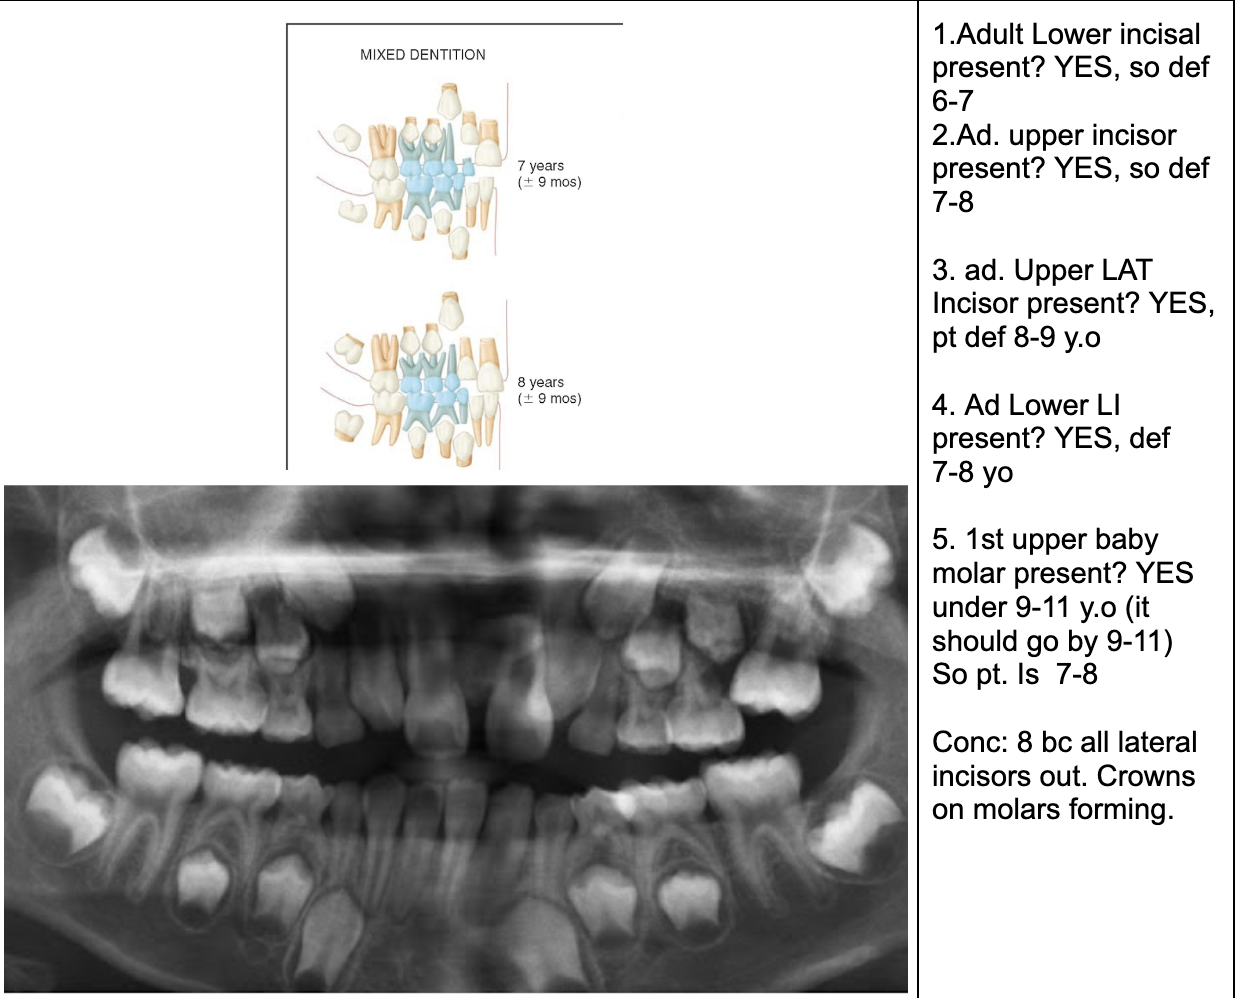

1.Ad. LOWER central incisors present? Yes. definitely 6-7 or older

1. Ad. UPPER CI present? Yes def. 7-8 y.o

3.Ad. Upper LAT incisor present (baby sheds 7-8)? NO so still under 7-8

Conc: pt is under 7